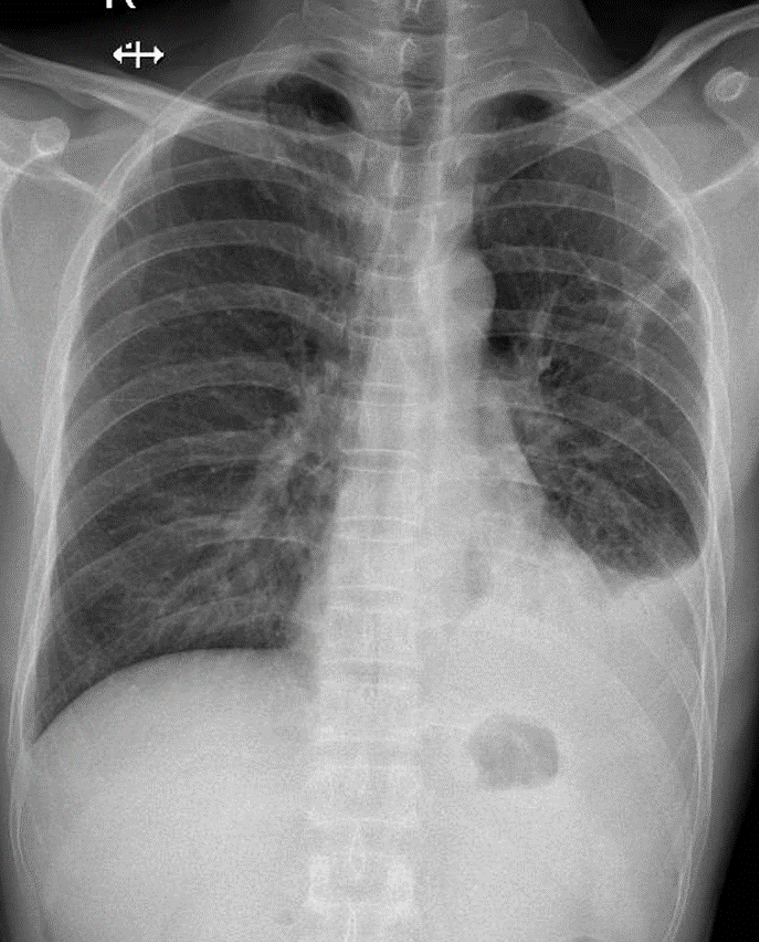

1-Xơ thùy trên phổi (T) 2-Tràn dịch màng phổi (T)